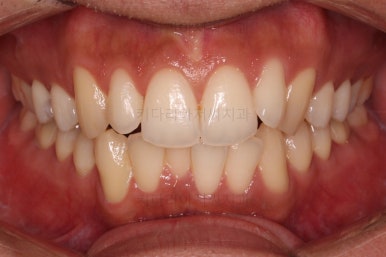

전후 비교해 보겠습니다.

교합이나 가지런한 느낌 매우 좋아졌고요.

특히 옆 라인에서도 둥글었던 윗입술도 오목한 곡선이 생기면서 돌출감이 좋아졌고 턱끝의 윤곽도 생기면서 무턱 느낌도 좋아졌습니다.

윗니의 위치를 보면 처음은 아랫입술에 가려질 정도로 아래로 내려와 있었는데 치료 후에는 앞니가 보이는 정도로 위치 조절이 잘 되었네요.

발치 없이도 문제점과 개선방향을 잘 셋팅한다면 이렇게 좋은 결과를 만들어낼 수 있답니다.